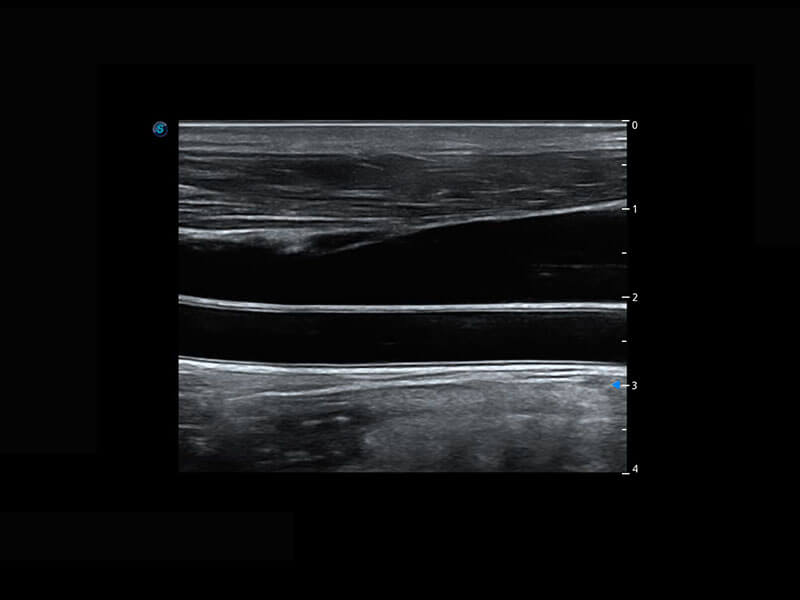

盆底超声

P60为盆底超声检查提供应用方案,多种腔内及腹部容积探头提供从二维、三维到四维的优异图像品质,实时快速三维容积数据获取,专业的测量工具包等人性化设计,为超声医生诊断提供有力保障。

Lev.Hiat A-r: 16.33 cm2

Lev.Hiat H-r: 53.70 mm

Lev.Hiat W-r: 43.96 mm

Lt-LUG-r: 24.16 mm

Rt-LUG-r: 19.94 mm

S-Pelvic

能够简化盆底检查的操作流程,可在二维模式及三维成像模式下实现一键自动提取出标准切面、自动识别当前切面、自动测量,提升盆底检查的高效性,同时也能让青年医生快捷的获得准确的检查结果。